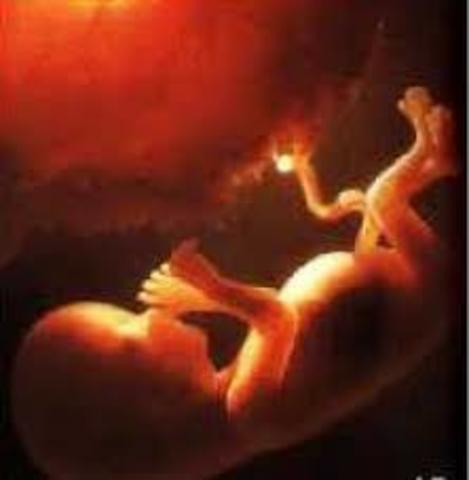

Hola Mamá, en esta semana tu bebé es casi un humano en miniatura, sus medidas alcanzarán los 21 cm de largo y llegará a pesar unos 550 gramos, sus pulmones están en desarrollo y segregan una sustancia llamada surfactante, que le ayudarán a introducir el aire en ellos cuando nazca. Recuerda que sus diminutos órganos se han ido formando, sus sentidos también están en pleno desarrollo, por lo que ya es capaz de sentir los estímulos que va recibiendo del exterior.

Háblale para que aprenda a reconoce